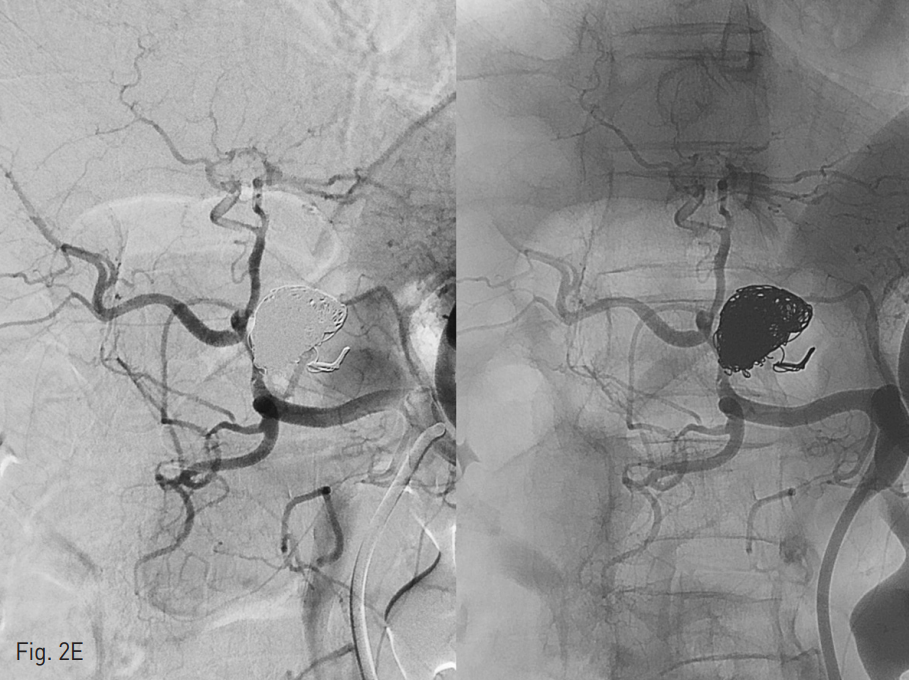

이 되도록 2.5 Fr Renegade (straight type)과 2.5Fr Renegade STS (angled ty pe)를 동시에 insertion하여 두 개의 catheter tip이 각각 동맥류 내부의 다른 위치에 위치하도록 navigation시킴 (Fig 2C). Balloon을 inflation시킨 후, 2개의 microcatheter를 통하여 interlock coils을 사용하여 embolization 시작함. Aneurysm neck으로 coil이 빠져 나오지 않도록 interlock coils을 사용하여 아주 주의 깊게 coil packing을 진행함. 최종적으로 직경 14mm ~3mm 크기의 interlock coils을 모두 24개를 사용하여 동맥류의 내부를 완전히 채움. Follow up celiac angiography에서 동맥류은 coiling packing되어 flow는 전혀 보이지 않았고, proper hepatic artery 의 flow는 유지되어 liver쪽으로 perfusion이 이루어지고 있는 것을 볼 수 있음 (Fig. 2E). Proper hepatic artery가 약간 가늘어 보이나, balloon inflation에 의한 vasospasm의 영향을 고려했을 때, 시간이 지나면 좀 더 좋아질 것으로 생각하고 시술 종료함.

Fig. 2. Balloon-assisted coil embolization

E. F/U angiography showed intact hepatic arterial perfusion without blood flow into the aneurysm.